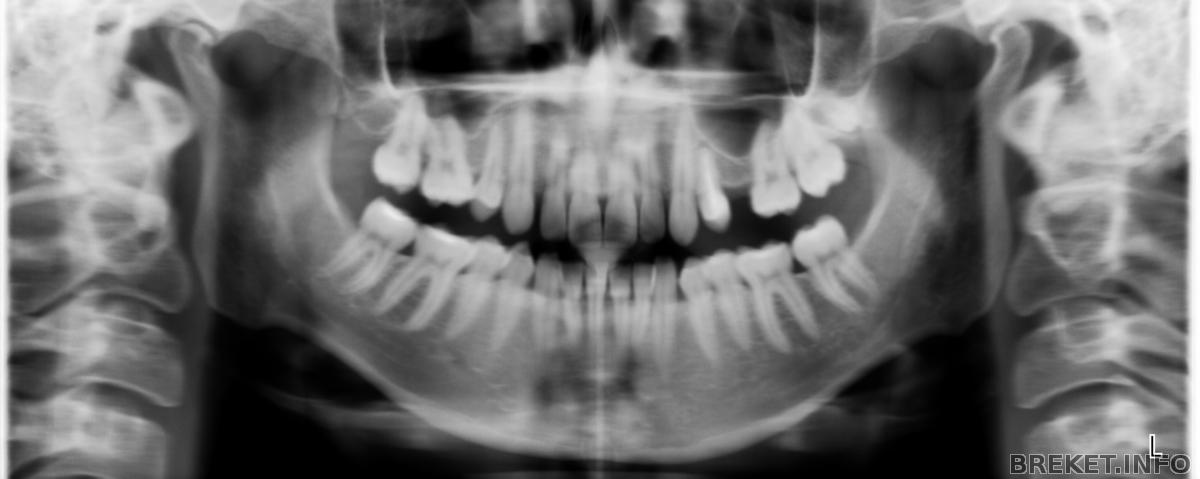

снимок До

.. нет двух пятерок на ВЧ, зубы поползли в стороны, с одной стороны щели очень большие и пустое место почти закрылось, да так, что протезист говорит, что места не сыскать для нового зуба ((... .. но какже быть? очень хочу убрать промежутки.. может был у кого похожий случай